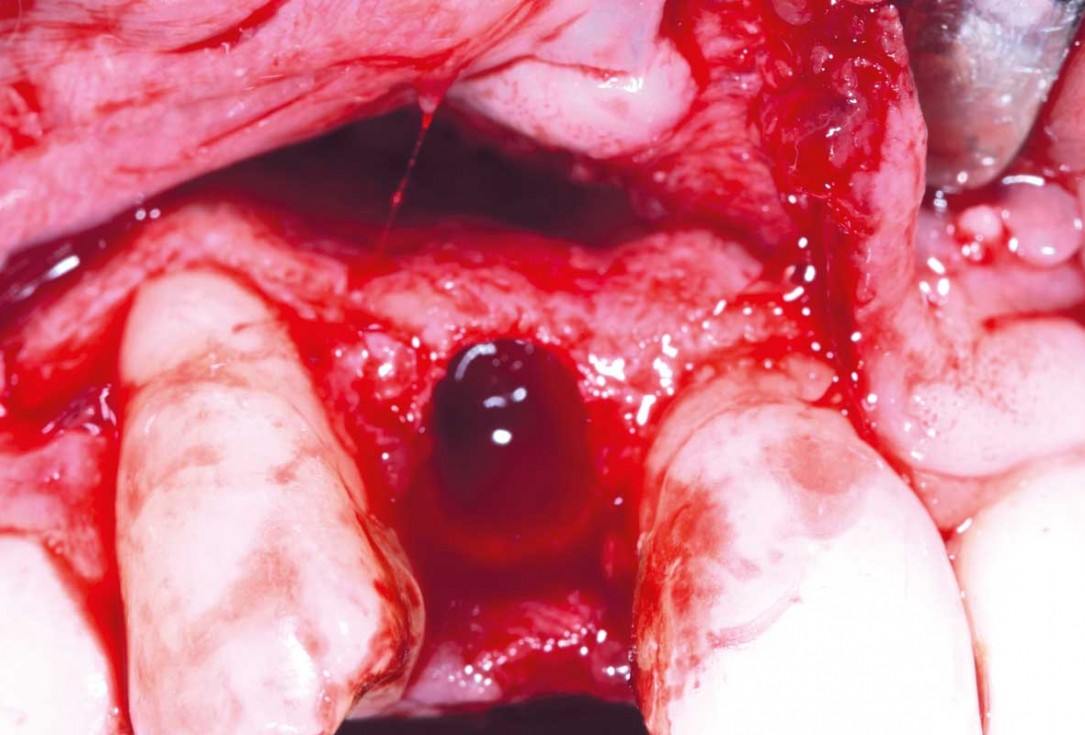

04/13 - Vertical extraction of tooth 12

Immediate implant placement in the maxilla with contour GBR - Dr. K. Loukas

05/13 - Full muco-periostal flap elevation